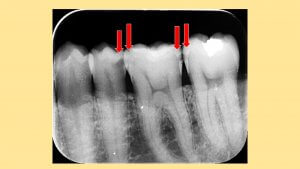

デンタルレントゲン撮影

大きな虫歯は視診で見つかることもありますが比較的小さなコンタクト直下に隠れている虫歯はレントゲン撮影で見つかることがあります。